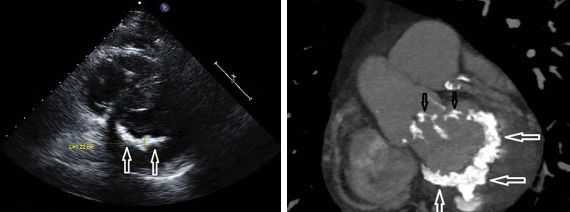

К малым аномалиям сердца причисляют всем известный, но вызывающий много вопросов своеобразный симптомокомплекс, диагностируемый преимущественно у детей - пролапс митрального клапана (ПМК). Сущность этого феномена состоит в нарушении функционирования сердечного клапана за счет прогибания (пролабирования) его створок в полость ЛП во время систолы желудочков. Кстати, пролабирование может быть замечено за любым из сердечных клапанов и даже за несколькими сразу (например, митральный + трикуспидальный). Одновременное прогибание нескольких клапанов усугубляет ситуацию, поскольку в подобных случаях формируются значительные гемодинамические расстройства.